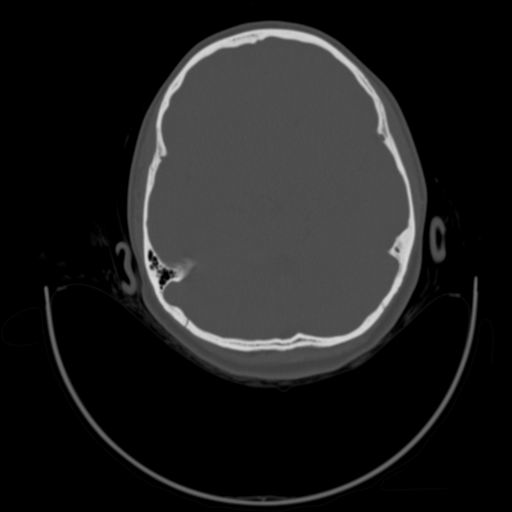

以下是引用随光逐影在2009-3-14 7:58:00的发言:[br]双耳——颞骨ct轴位平扫未见明确异常。